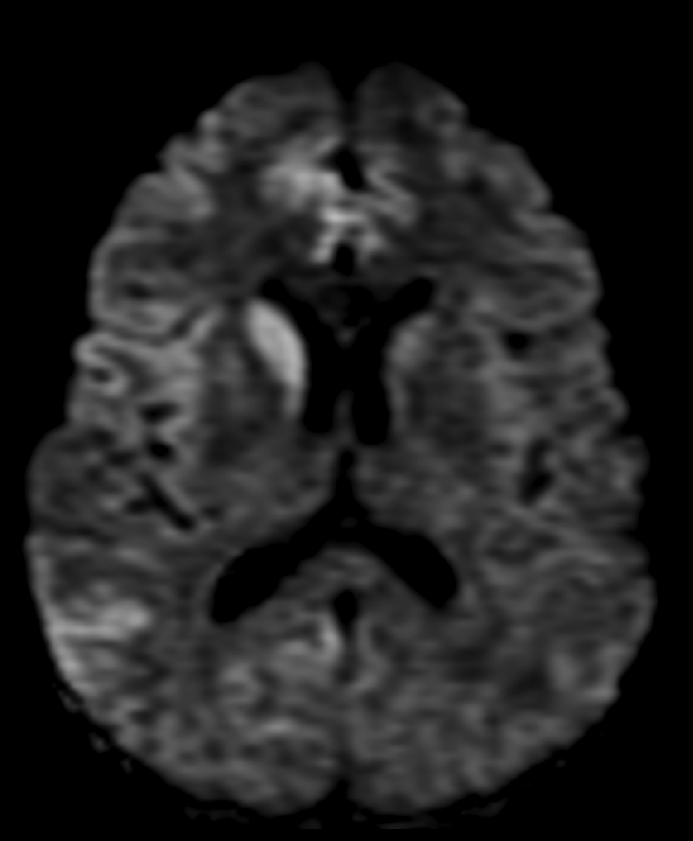

Paciente de 48 años con demencia rápidamente progresiva.

- D. Enfermedad de Creutzfeldt-Jacob con alteración de señal asimétrica en núcleo caudado y cortical frontotemporal.

- C. DW-EPI.